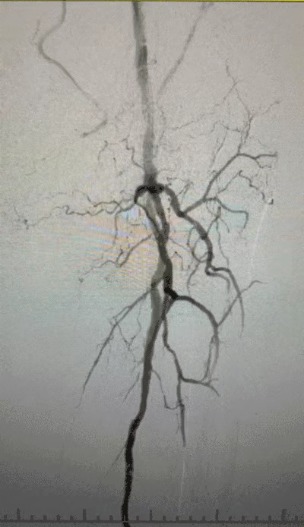

· Imagem pré-operatória: estenose calcificada difusa grave em artérias bilaterais dos membros inferiores

Dada a condição vascular complexa, selecionamos o ThorCrack Peripheral IVL Balloon Dilatation Catheter System. Devido à limitada tolerância do paciente, foram realizados procedimentos intervencionistas estadiados em ambos os membros inferiores.

Resultado cirúrgico

Pós-procedimento, a estenose arterial melhorou significativamente, o fluxo sanguíneo aumentou e a temperatura da pele aumentou. Nenhuma complicação pós-operatória ocorreu. Tanto o paciente quanto a equipe cirúrgica ficaram muito satisfeitos com os resultados.